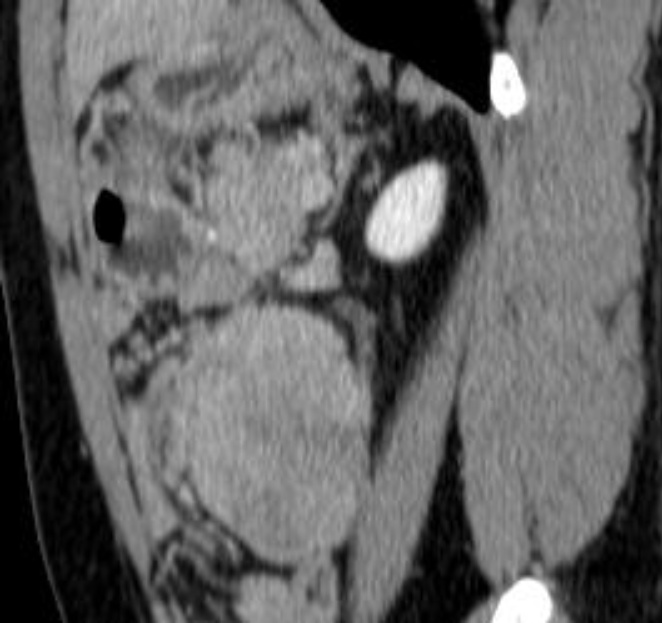

患者男,41岁。1年前气管插管全麻下行腹腔镜全大肠切除术,术后病理提示:家族性腺瘤样息肉病伴乙状结肠中分化管状腺癌。术后行“奥沙利铂 + 卡培他滨”化疗6次,化疗期间肿瘤指标正常。1年后复查全腹CT所见:左肾前下方及肠系膜内亦见多发肿块,较大者位于左肾前下方,大小约2.7 cm × 2.3 cm × 3.6 cm (左右径 × 前后径 × 上下径),边界光整,等密度;动脉期轻度强化,内见血管穿行;静脉期及延迟期呈渐进、延迟不均质强化,内见低密度区,肿块与左侧输尿管上段分界不清,以上肾盂积液轻度扩张,再经3个月后,复查全腹CT (图1图2)提示腹腔肿块明显增大,病灶大小约6.6 cm × 5.7 cm × 8.7 cm (左右径 × 前后径 × 上下径)。随后完善腹部MR (图3),所见:左肾前下方见及肠系膜内亦见多发长T1不均匀长T2信号影,弥散未见明显受限,增强扫描呈渐进性不均匀强化,内见无强化坏死区,肿块局部向后压迫左侧输尿管上段并分界不清,以上输尿管及肾盂轻度积液扩张。综合CT及MR影像诊断:转移瘤可能性大。但患者体重稳定增加,复查肿瘤指标仍未见异常,影像诊断与临床不符。

Figure 2. Plain CT and dynamic contrast-enhanced CT imaging in the sagittal plane

2. CT平扫及动态增强矢状位

计算机断层扫描(Computed Tomography, CT):CT平扫通常表现为边界不清或境界较清的软组织密度肿块,密度多为等或稍低于肌肉密度,内部可见条索状或斑片状低密度区(代表黏液变性或坏死,相对少见)。增强扫描动脉期轻度强化,静脉期及延迟期呈进行性不均匀强化,这与肿瘤富含纤维组织、对比剂缓慢渗透有关。对于腹腔内病变,CT可清晰显示肿瘤与肠管、血管的关系,评估有无肠梗阻、肾积水等并发症。但CT对软组织分辨率有限,对肿瘤内部结构细节的显示不如MRI。